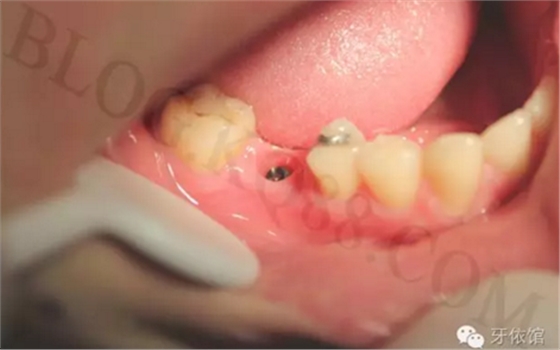

術(shù)后三個月的口內(nèi)照片。

卸下愈合基臺,可見袖口干凈整潔。

安裝印模帽(開放式)。